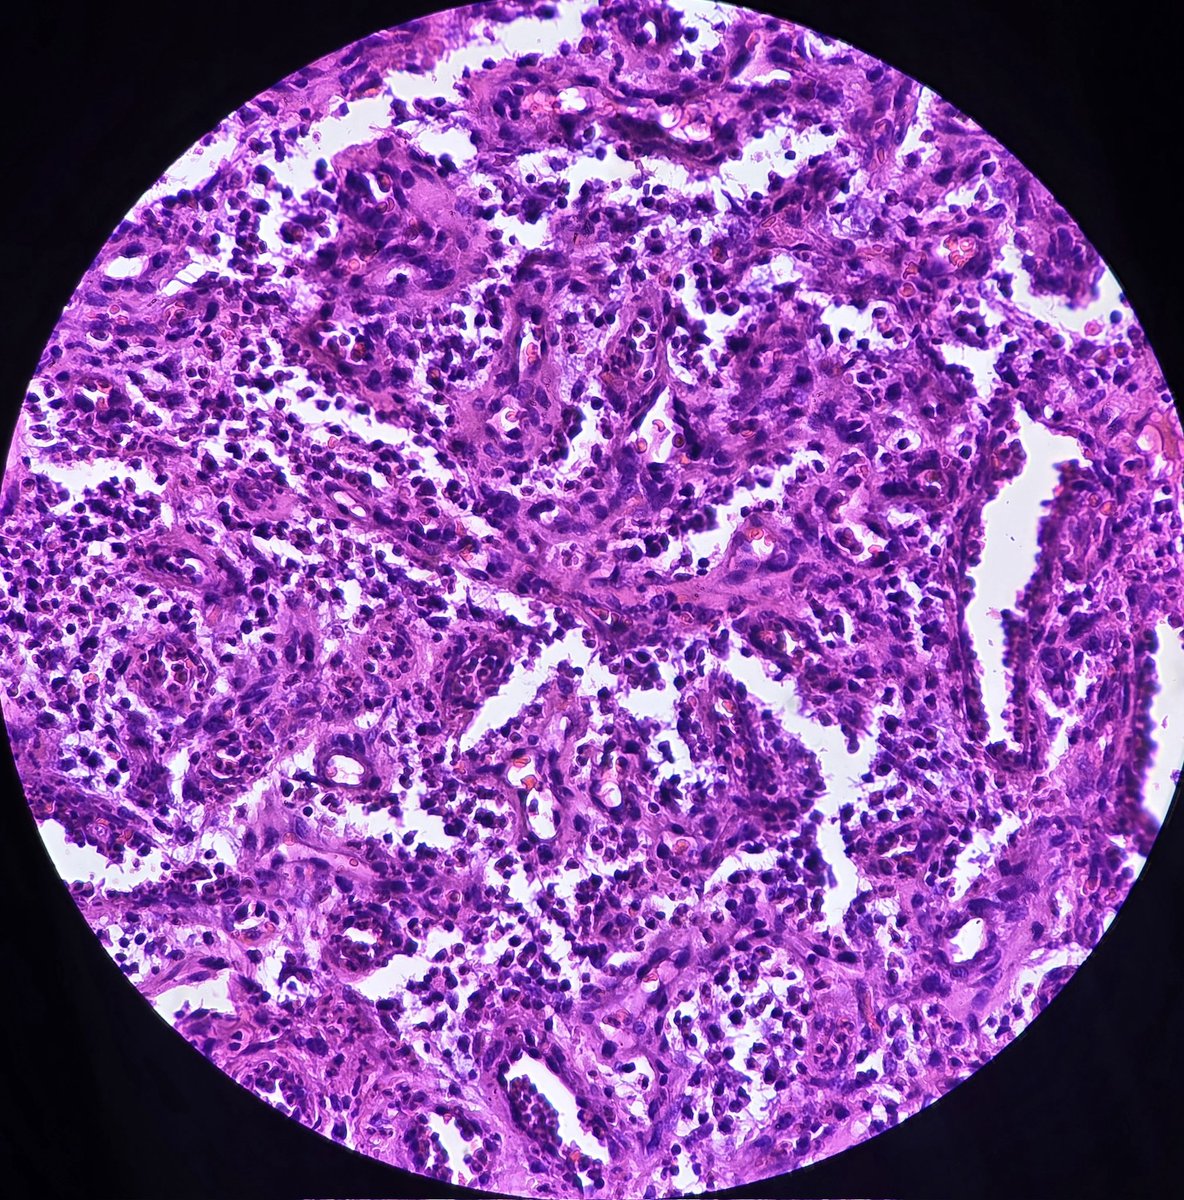

Nodal metastasis of poorly differentiated gastric carcinoma: Presence of poorly cohesive cells (some are signet ring forms) in subcapsular lymphatic sinus.

#Pathology #GIPath